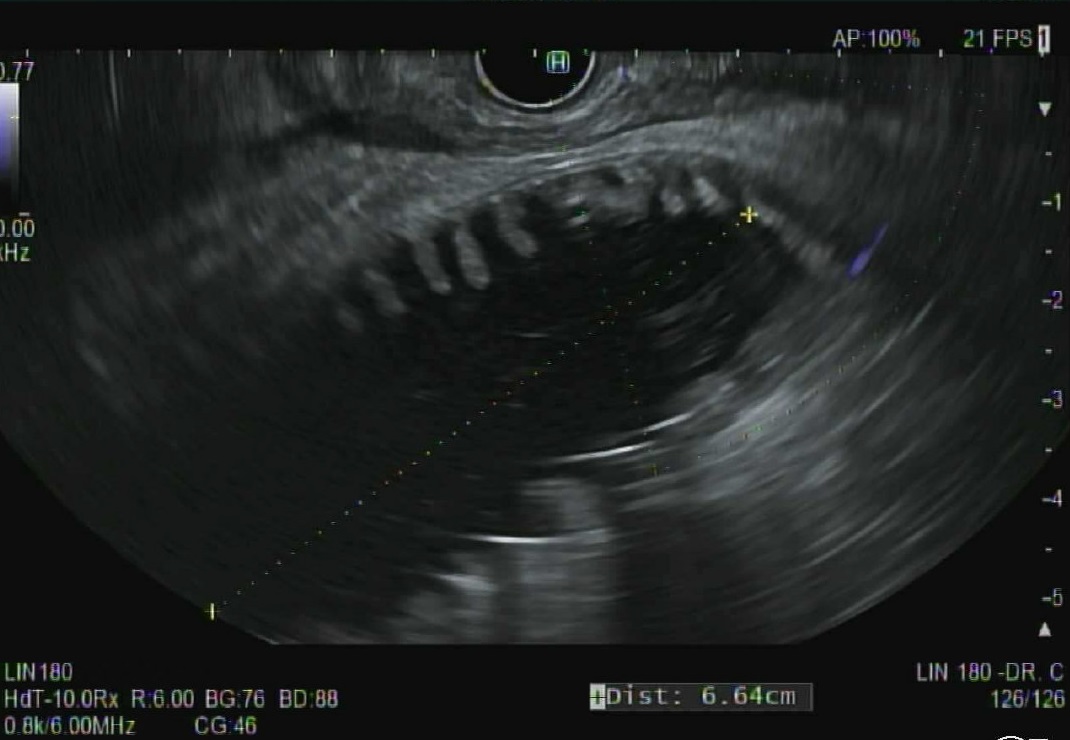

@SChandanMD

3 days

EUS guided gastroenterostomy has ✨revolutionized✨ management of malignant gastric outlet obstruction Grateful for my training at #CIE @AdventHealth allowing me to bring this intervention to our #WestHouston community patients! 📈 PO intake ⬇️ Symptom recurrence #GITwitter